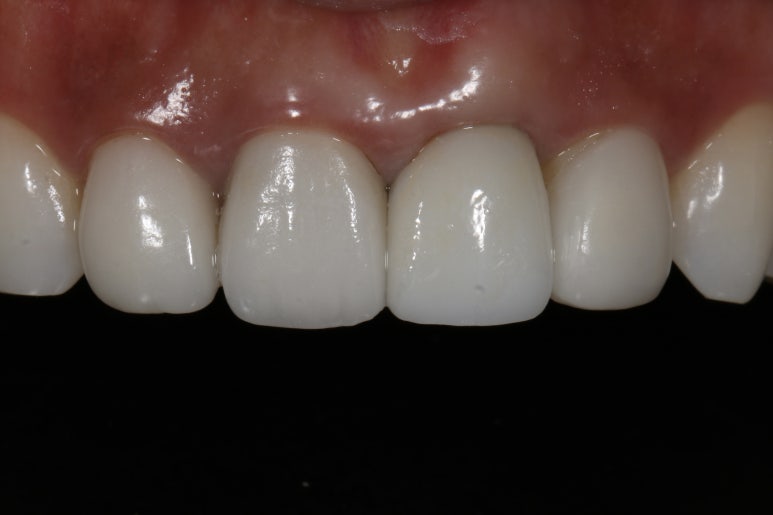

보철물 완성 사진

마지막으로 보철물까지 올린 후에 완성 사진을 찍었답니다.

잇몸 높이가 옆 치아와 대칭성을 이루는 부분이 사실 가장 관건인데 이 부분이 잘 이루어진 것을 확인할 수 있답니다.

전후 비교 사진_ 잇몸 높이가 달랐던 술전 상황과는 달리 임플란트 수술 후에 잇몸 높이가 같아진 것을 확인할 수 있음

다행히 이렇게 케이스가 잘 마무리되었고요, 저희 병원 같은 경우 앞니 보철을 원내 제작하기 때문에 색조와 모양도 만족스럽게 마무리가 잘 되었답니다.